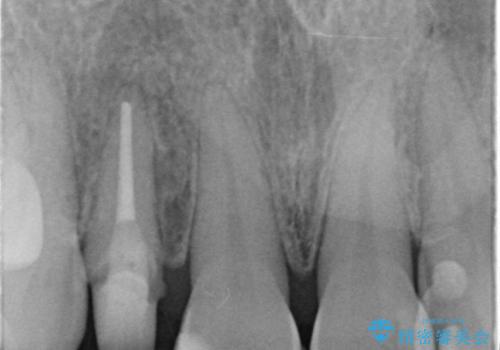

- 右上の前歯が取れたとのことで来院された患者様です。

再根管治療からのやり直しをご提案しましたが、ご希望されなかったため土台(コア)のやりかえからとなりました。

- 右上2 仮歯/11,000円 ファイバーコア/22,000円 ジルコニアクラウン(スペシャル)/154,000円 合計187,000円費用は治療当時の料金となります